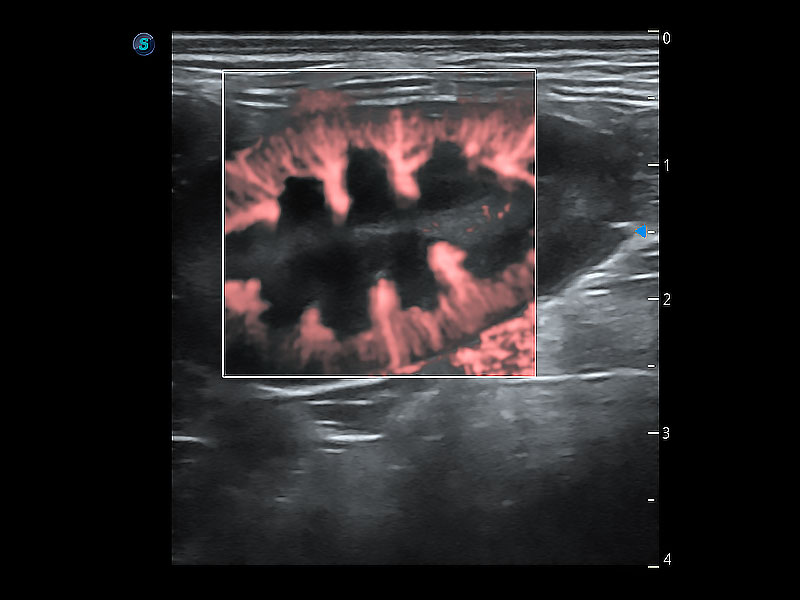

高性能和先进的临床应用工具可以为动物医生提供临床信心。ProPet 80 搭载了先进的腹部和浅表应用工具,帮助医生在日常临床实践中发挥前所未有的作用。

极大提升超低速微细血流的检出能力,同时更精准地滤除软组织和超声信号,为兽用医生提供以往无法通过常规血流获得的疾病诊断信息。

在传统二维血流成像的基础上,呈现血流的立体感,具有动感的生命力之美。即便是微小的血管也能轻松应对,提高了血流的视觉敏感性。